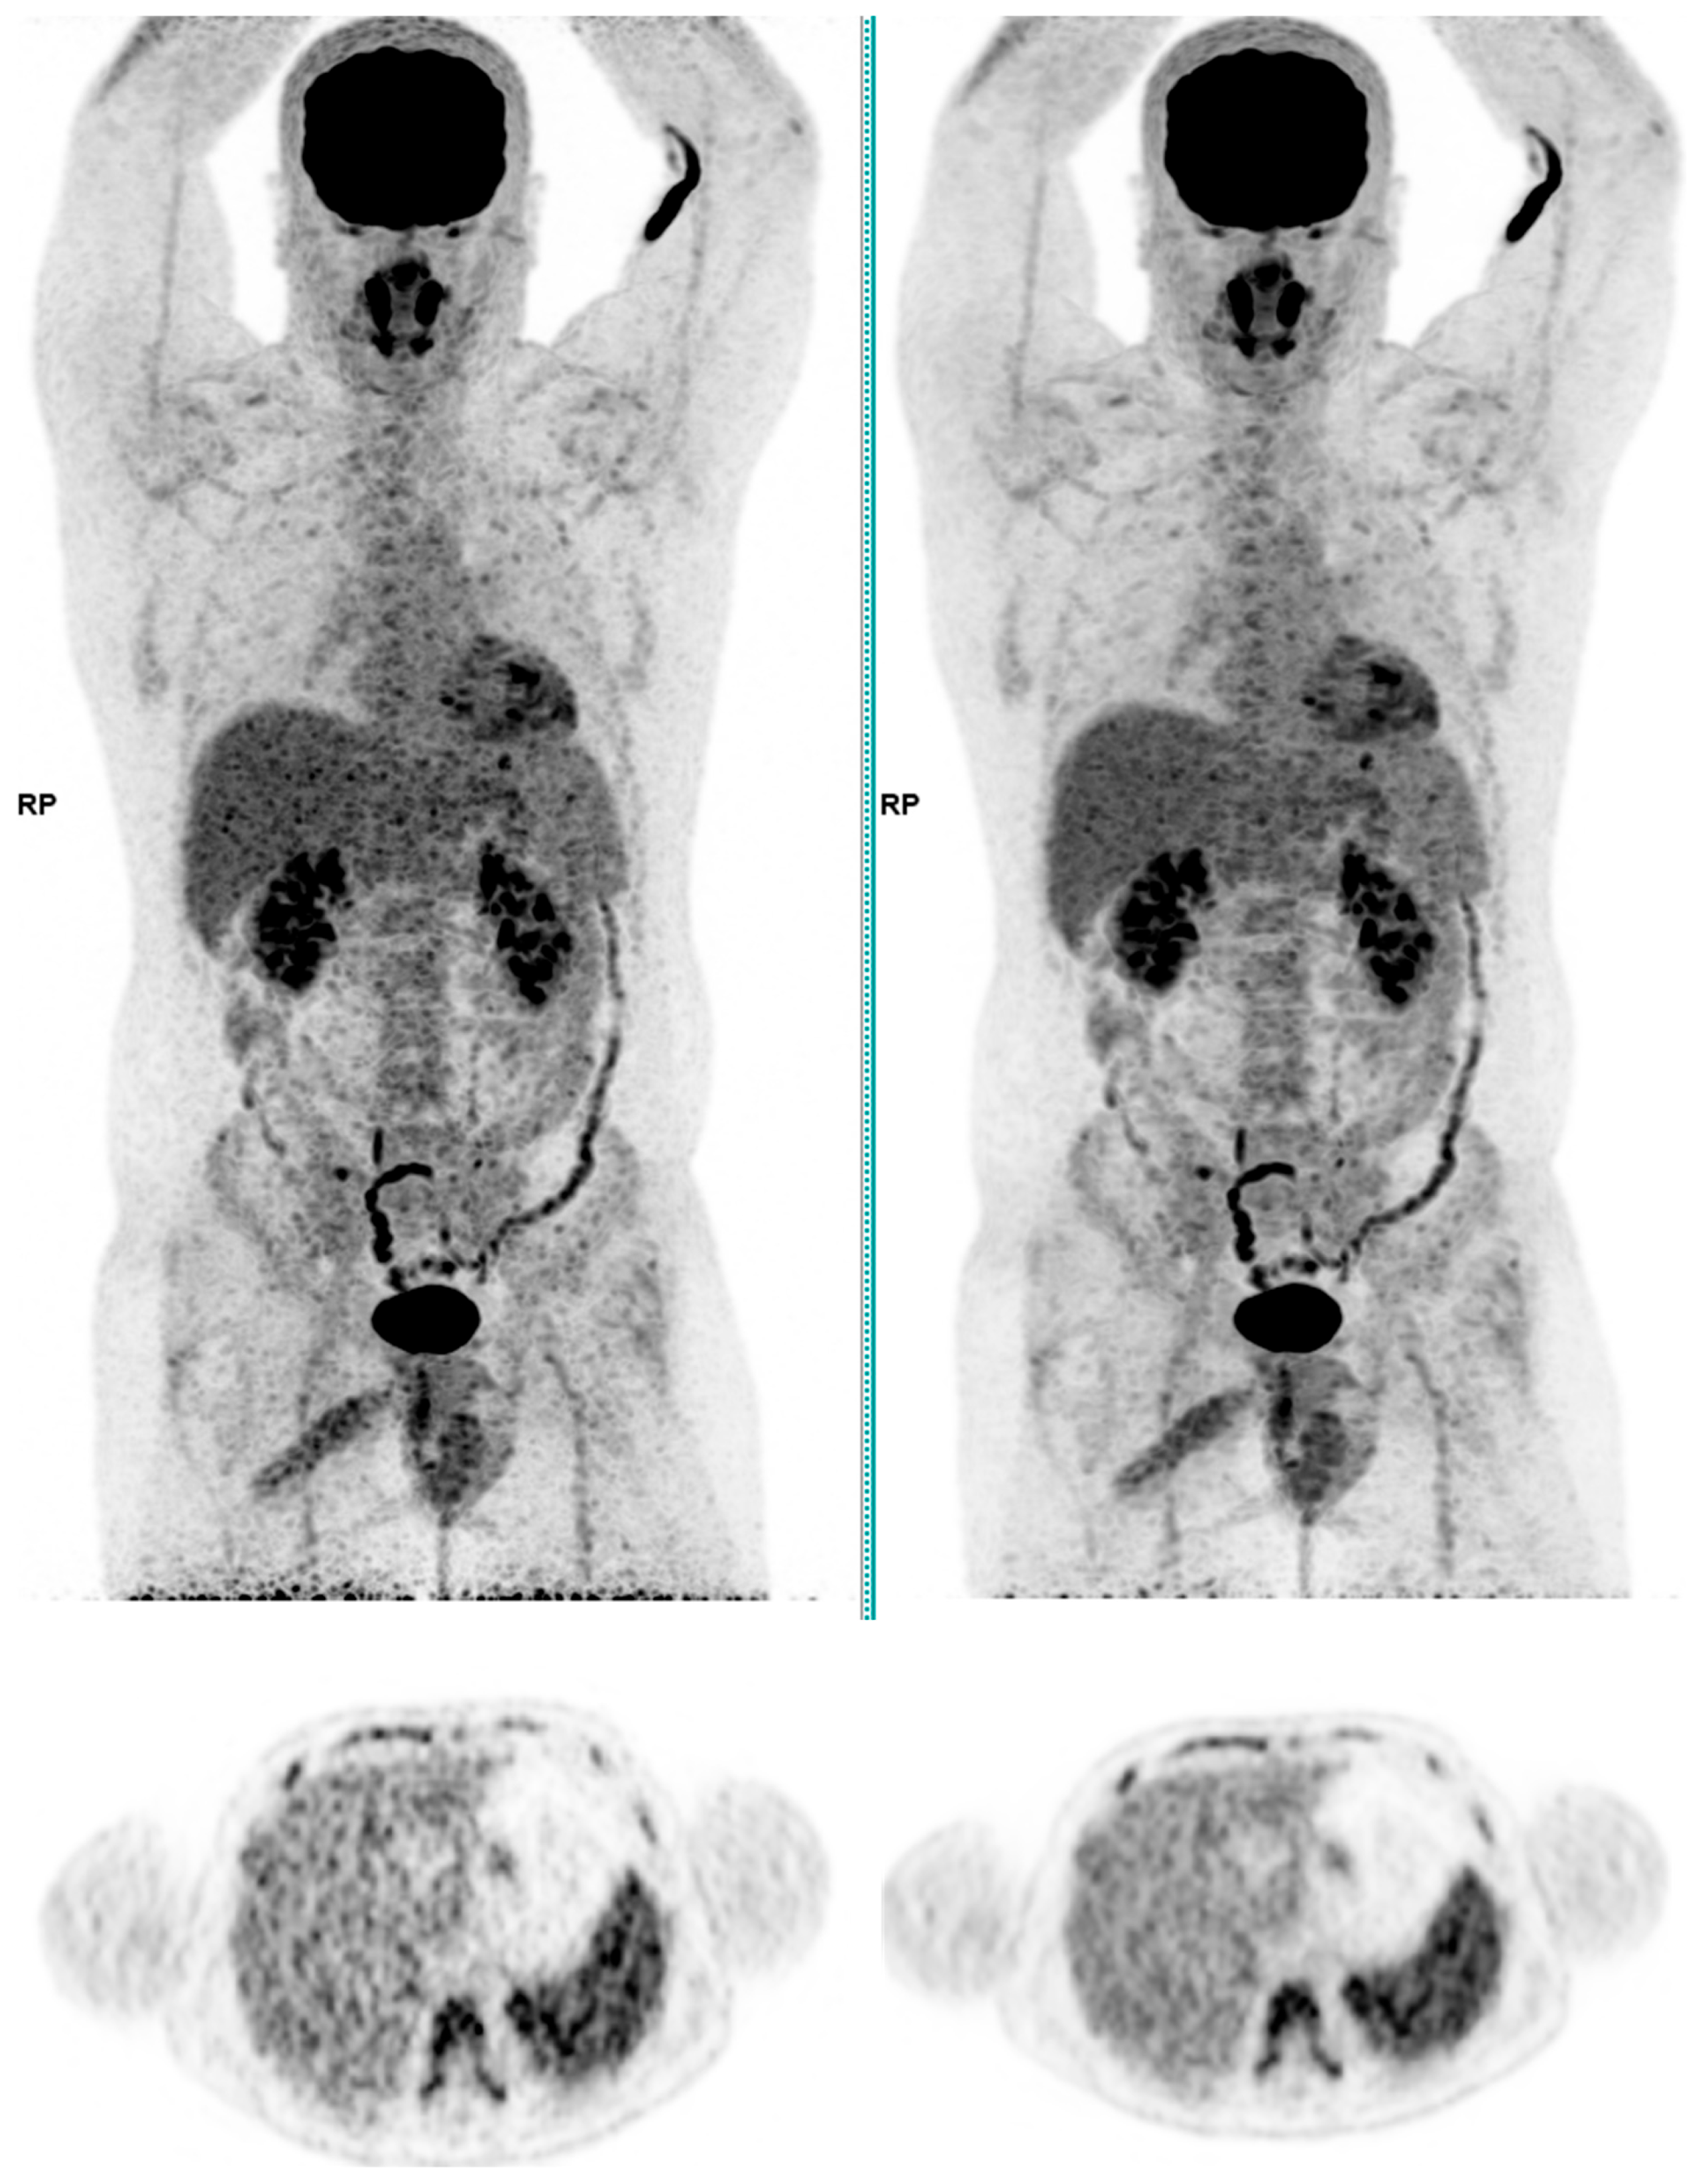

Across the three radiotracers, the AI-denoised images demonstrated a significantly improved performance in the visual analysis compared to conventional PET images. AI-denoised images were rated as interpretable (scores of 3–5) in all cases, compared to 65% for conventional images. Furthermore, an excellent image quality (score of 5) was achieved in 85% of all AI-denoised images, a significant improvement compared to the 50% in standard acquisitions. SubtlePET™ processing resulted in consistently lower noise levels, particularly for 18F-FDG scans, where 85% of images scored 4 or 5 for noise reduction compared to 60% in conventional scans. Lesion detectability was maintained or enhanced across all radiotracers, ensuring no compromise in the diagnostic accuracy. For 18F-FDOPA, a tracer with inherently lower signal-to-noise ratios, the AI algorithm improved the detection confidence by 25% compared to standard protocols. The visual comparison is illustrated through different MIP images and transaxial images (Figure 1, Figure 2, Figure 3 and Figure 4)

Figure 2. Total body 18F-FDG PET CT, MIP and transaxial images (left: without AI denoising; right: with AI denoising).

Jimaging 11 00234 g002